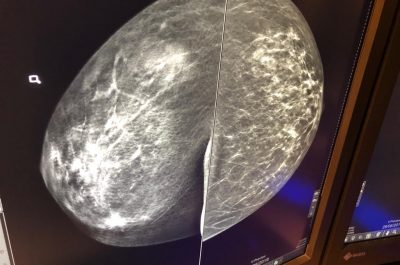

Mammografia 3 D, scoprire i tumori “invisibili”: ecco come funziona e quando è necessaria la tomosintesi